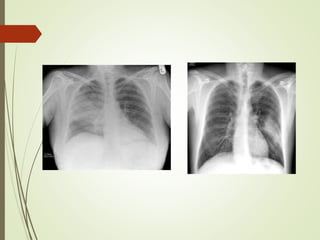

 Chest xray

Diagnostic approach  Chestxray  Sputum examination  Blood culture sensitivity: high risk patient as neutropenic, asplenia,complement deficiency,CLD or severe CAP  Antigen test: for pneumococcal and certain legionella antigen in urine  PCR: detect neucleic acid of legionella spp., M.pneumonia